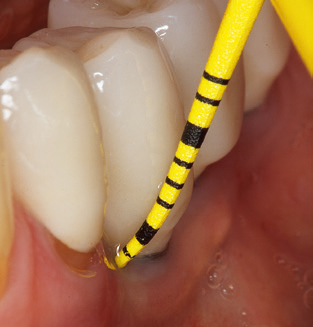

Das aktuelle Arbeitskonzept für die UPT

Die gute Ausleuchtung des Arbeitsfeldes stellt eine wesentliche Erleichterung dar. Bei dem von den Autoren genutzten System ist dies gelungen, indem ein 5facher LEDRing in das Handstück integriert wurde. Natürlich werden für dieses System unterschiedliche Arbeitsspitzen für die jeweiligen Indikationsbereiche angeboten. Eine gerade, universell einsetzbare Spitze ist das Basisinstrument zur maschinellen Instrumentierung natürlicher Zähne (Abb. 5a und b). Für schwer zugängliche Bereiche im Seitenzahnbereich werden gebogene Spitzen angeboten, die auch einen Zugang zu freiliegenden Furkationen ermöglichen (Abb. 6).